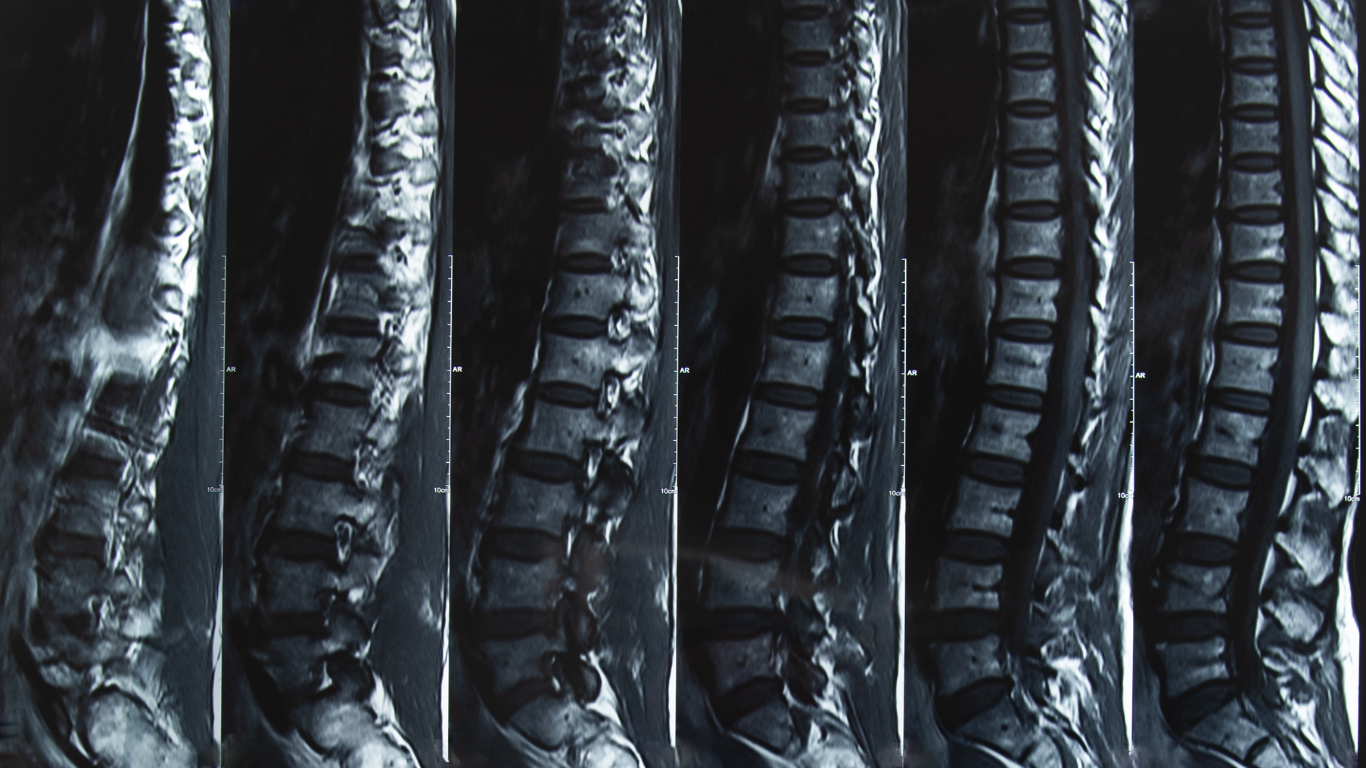

Magnetic resonance imaging (MRI), a test that uses a magnet field and pulses radio wave energy to take pictures of the organs and structures within the body, is called magnetic resonance imaging. In many cases, MRI provides information that is not available with the computed tomography scan (CT) scan. MRI may also reveal problems that are not visible with other imaging methods.

- Imaging organs and soft tissue internal structures (see the spine scan image to right)